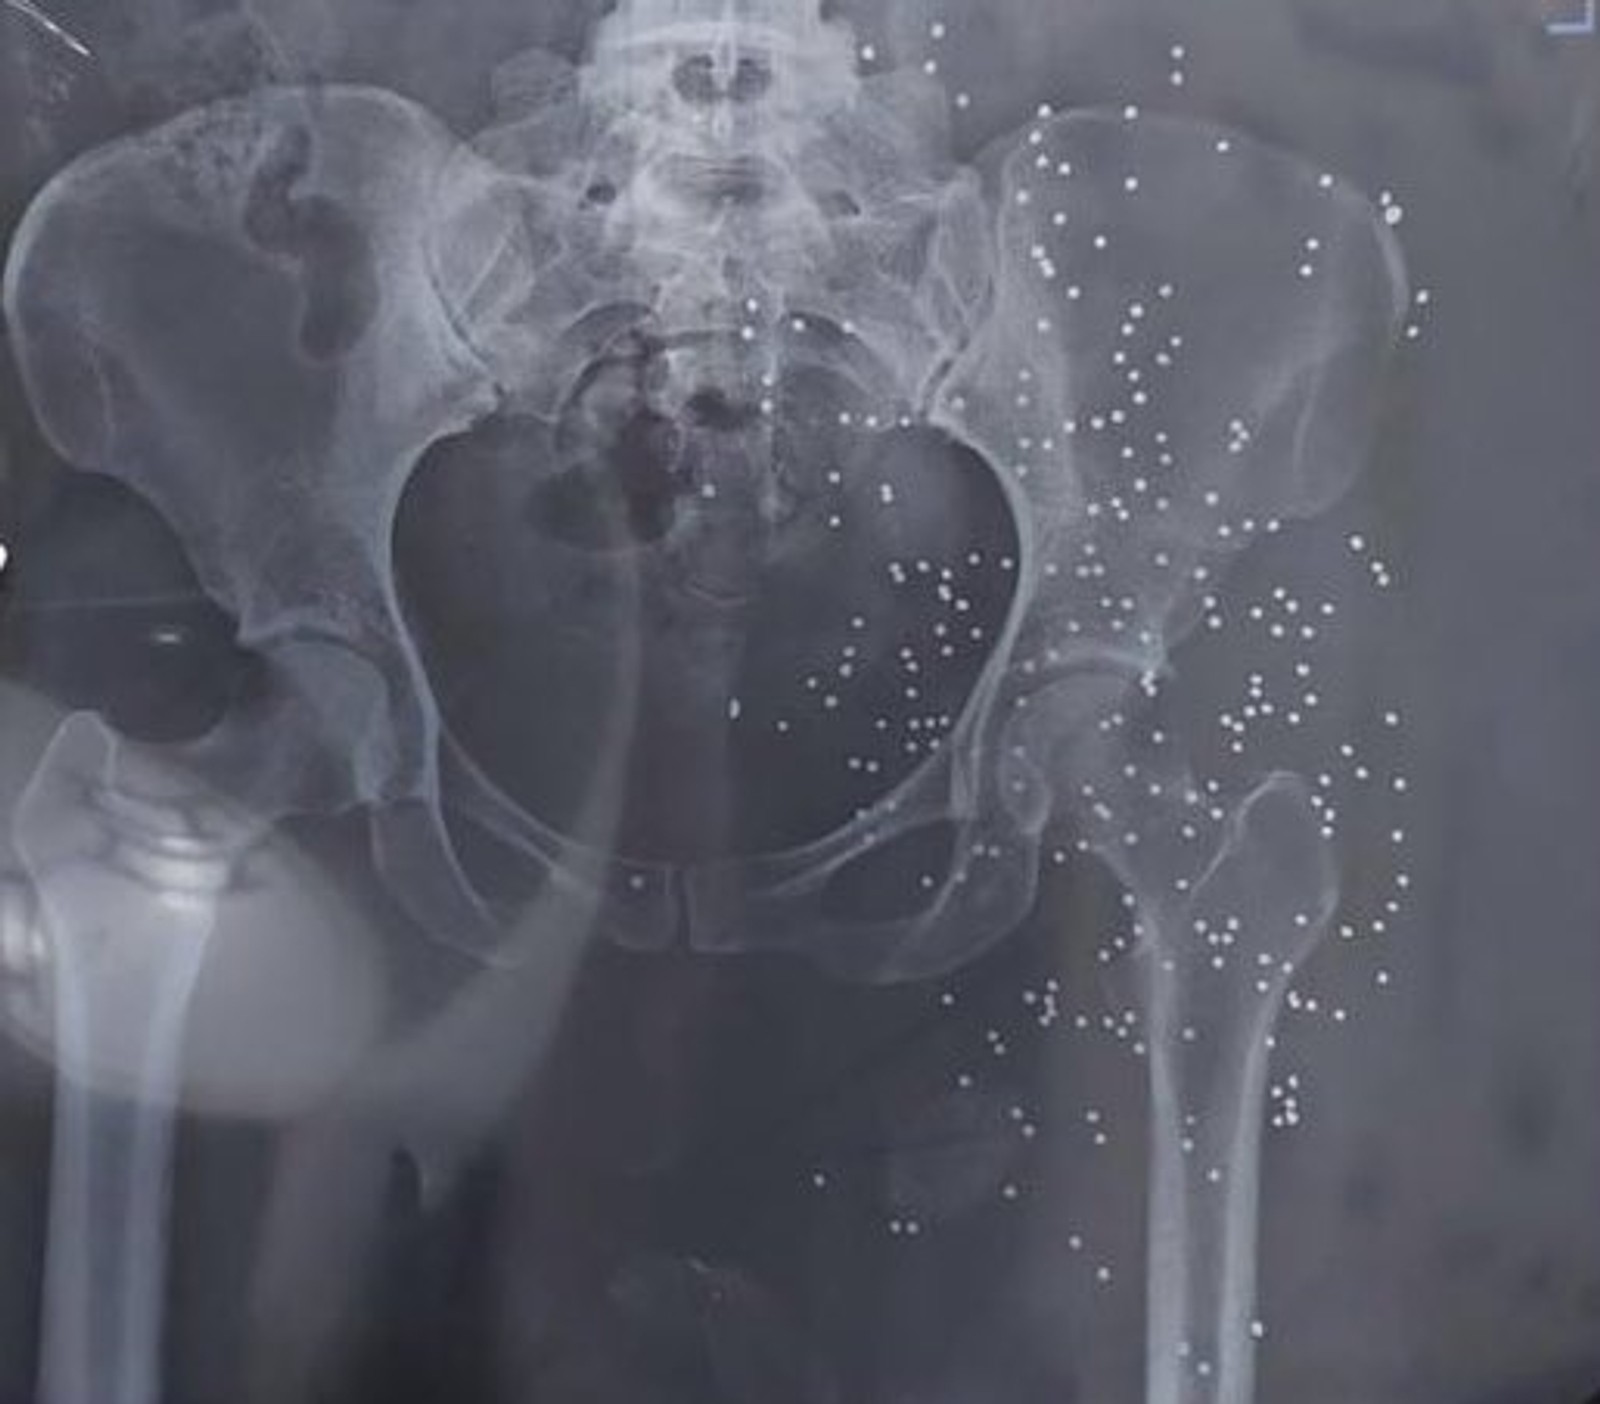

In addition to photos and videos of the injuries, the batch includes dozens of x-ray images and CT scans of pellets and slugs in the head, neck, chest and legs of the protestors. The Islamic Republic has killed many protesters with rubber bullets and metal pellets and blinded so many others.

The regime’s security forces have been extensively using cartridges of shotshell loaded with numerous small balls or birdshots, or medium-sized buckshots as well as single large solid projectiles known as a slug to quash the nationwide protests, ignited by the death in custody of 22-year-old Mahsa Amini in September 2022.